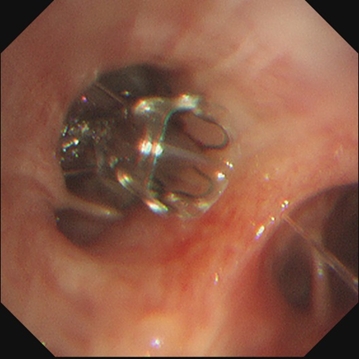

▲术中情况